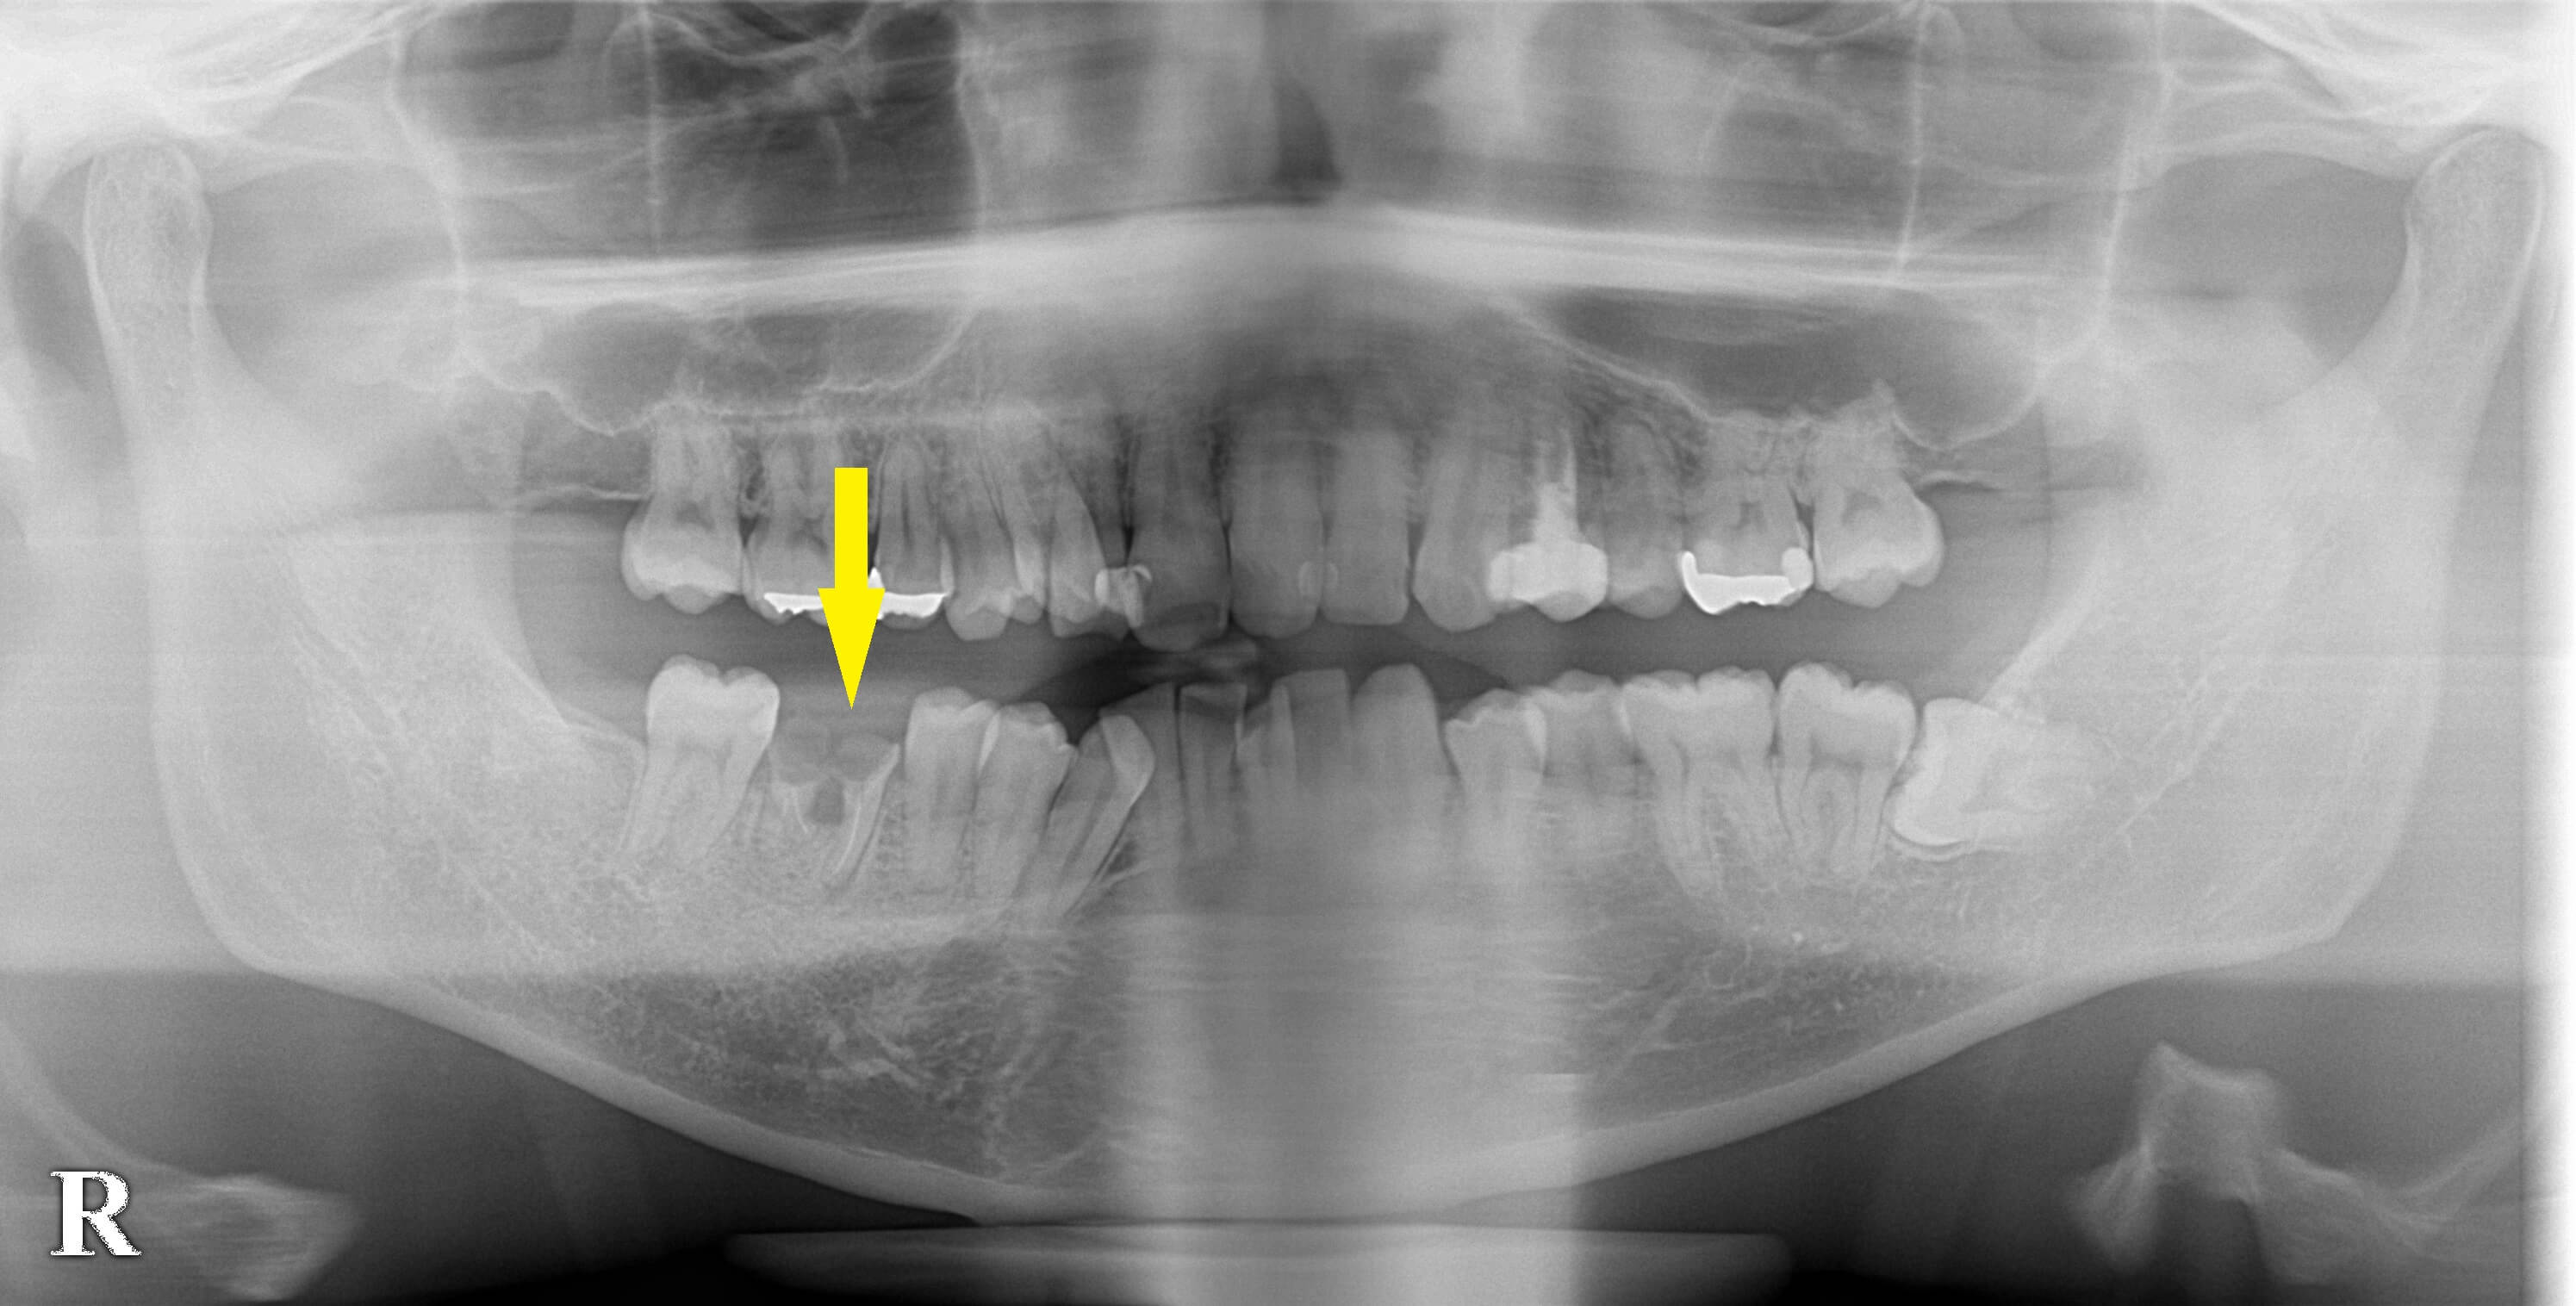

右下顎の第一大臼歯が、神経を抜いて治療されていたのですが、被せものがはずれ、根っこだけが残っているという状態になってしまいました。

保存は不可能でしたので、抜歯してインプラントかブリッジか義歯ということになります。

両隣の歯がきれいですので、これを削ってブリッジにするのは避けたいところです。